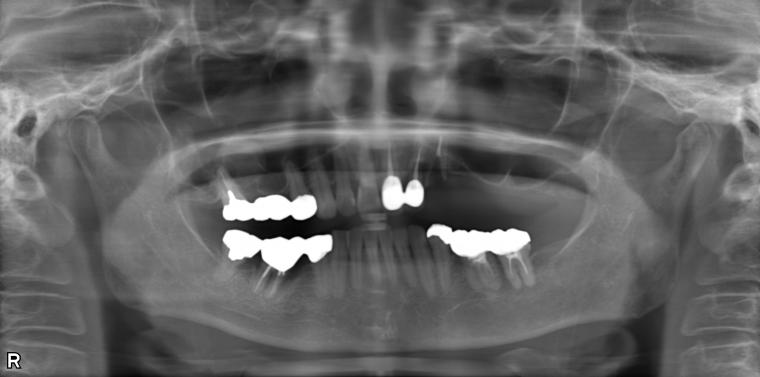

BEFORE

65歳女性/上3本欠損/インプラント埋込手術

被せ物が取れて来院された患者さんです。

上顎犬歯の保存が厳しい状態だった為抜歯となりました。

ご来院時から欠損状態だった左上第一小臼歯から第一大臼歯も含め、欠損補綴についてお話させていただき、

インプラントでの治療を選択されました。